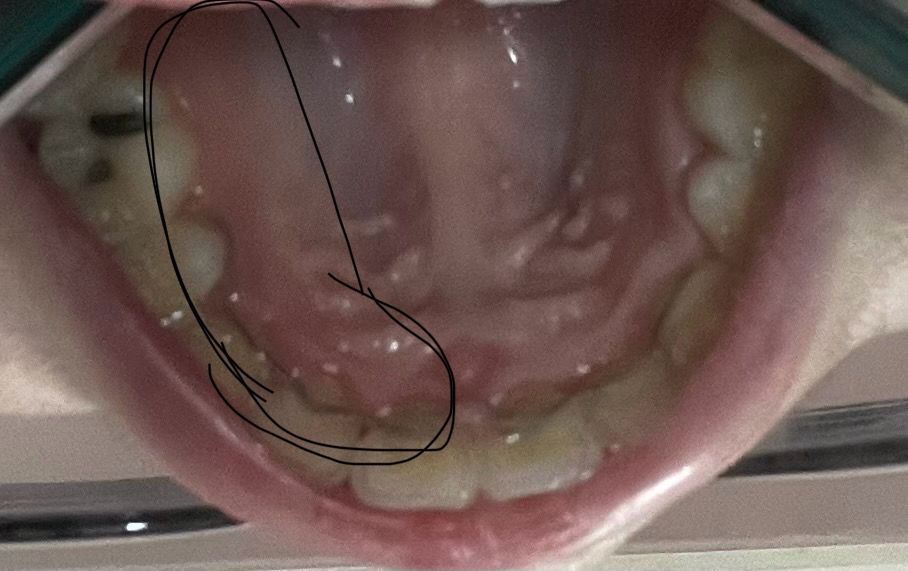

앞니 뒷쪽(입천장)잇몸이 자꾸 부어요

음식 먹을 때랑 양치한 직후, 자고난 직후는 괜찮는데 시간이 좀 지나면 자꾸 저기가 부어요

3. 혹시 교정 고정식 유지장치 위치가 문제가 있나요?

• 1번 째 사진